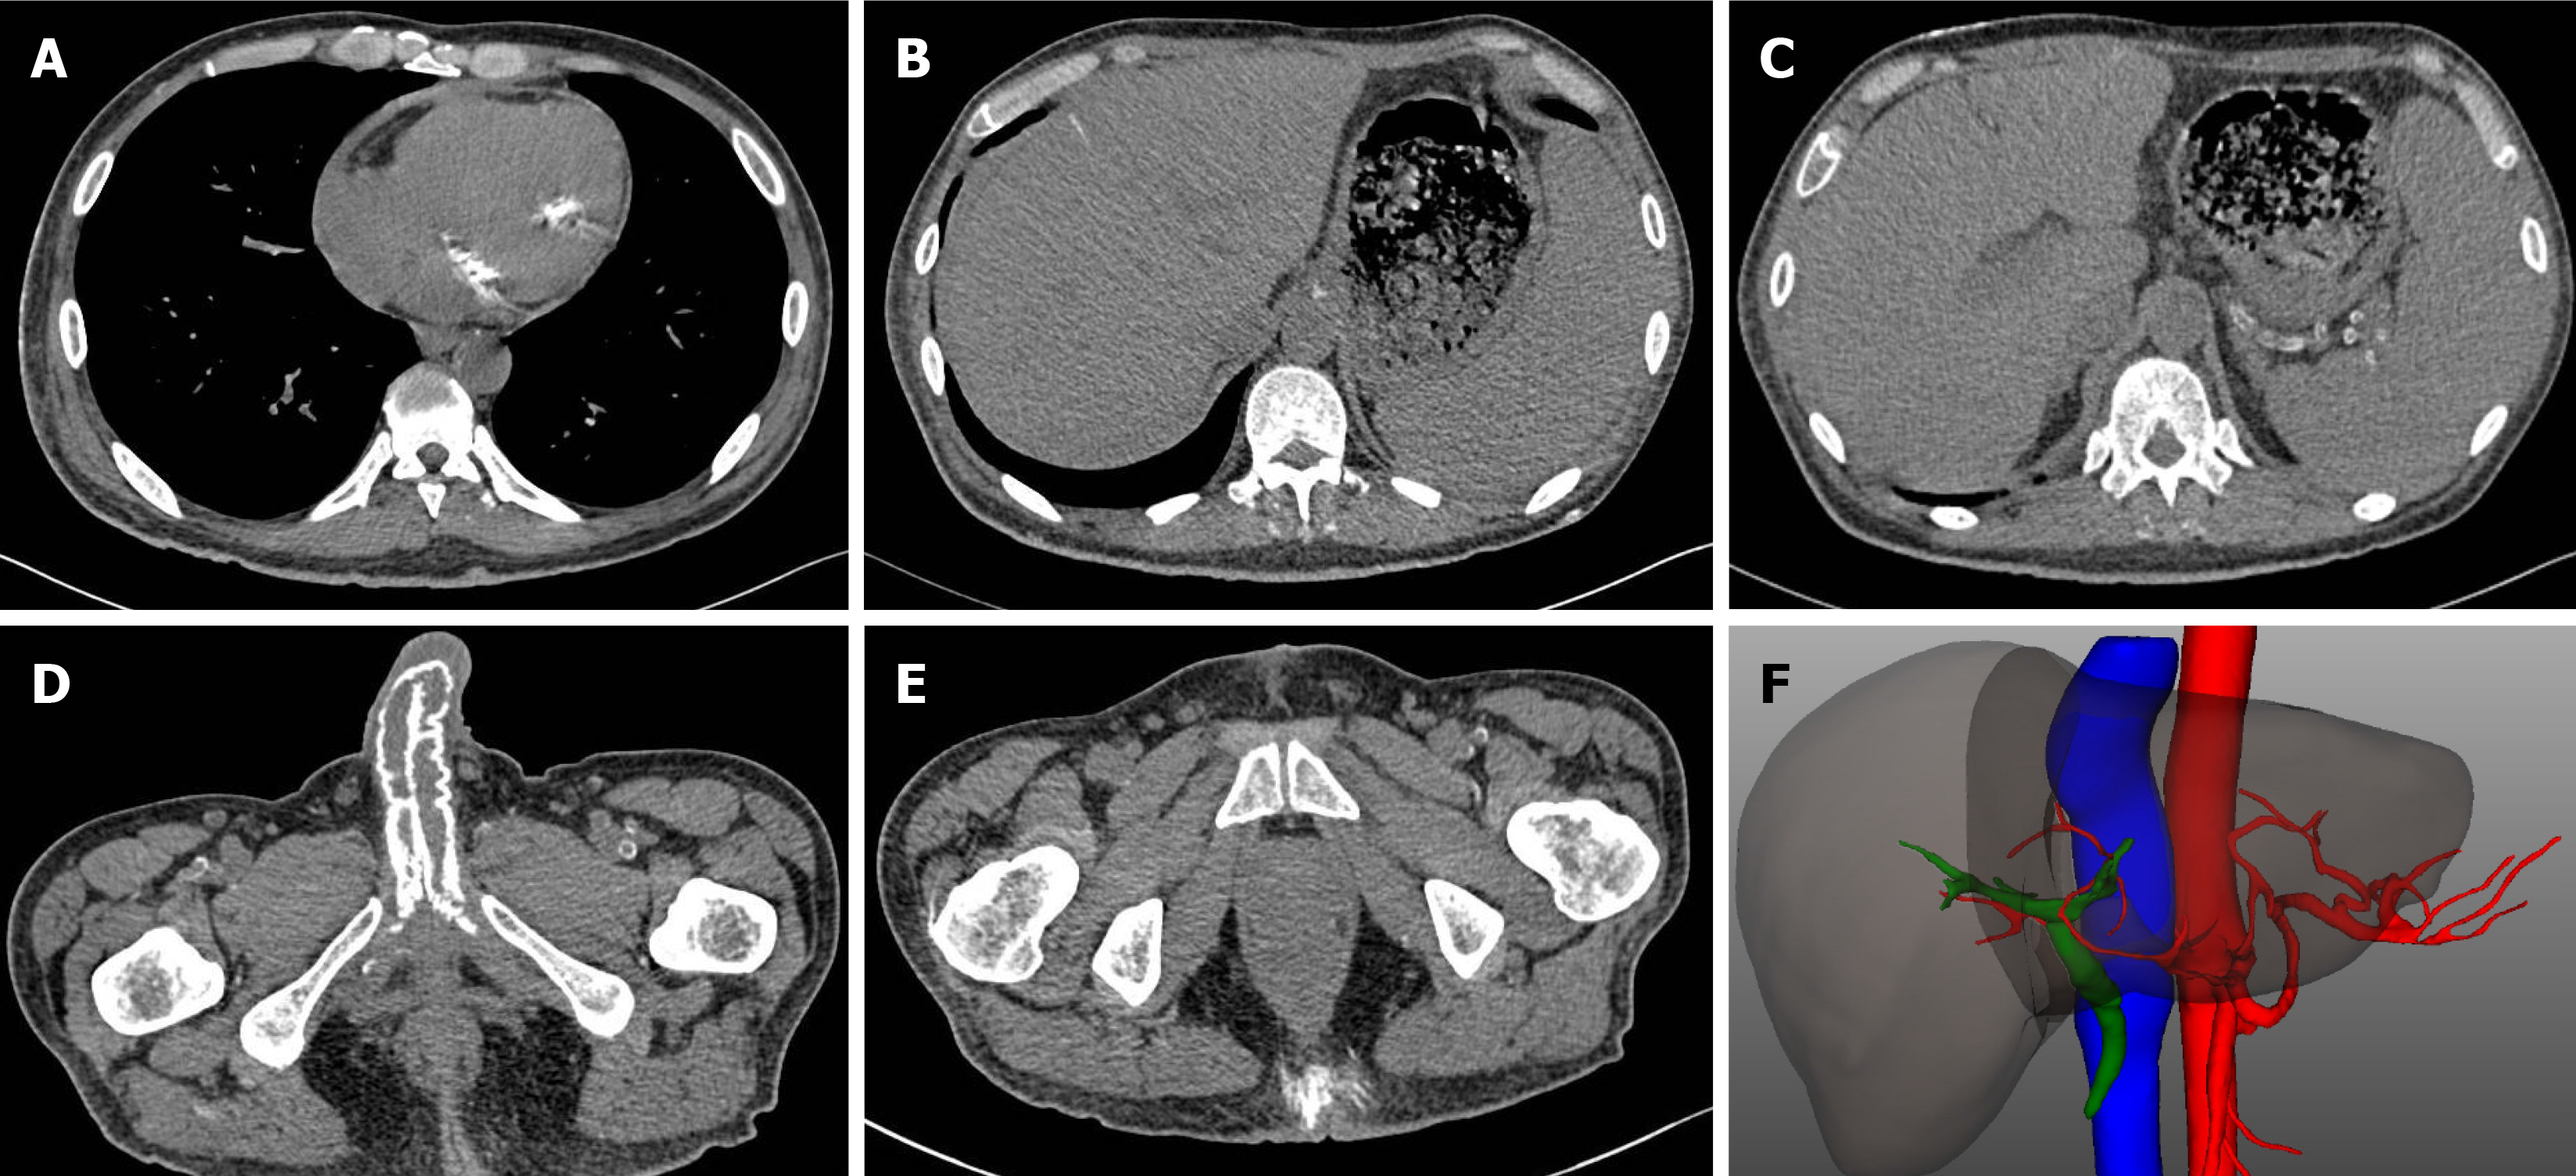

Figure 3 Computed tomography images.

A: Calcification of the bicuspid valve; B: Calcium deposit in the liver; C: Calcification of the splenic artery; D: Calcification in the penis; E: Calcium deposition in the subcutaneous tissue of hip area; F: 3D reconstruction of computed tomography showing occlusion of branches of hepatic arteries.